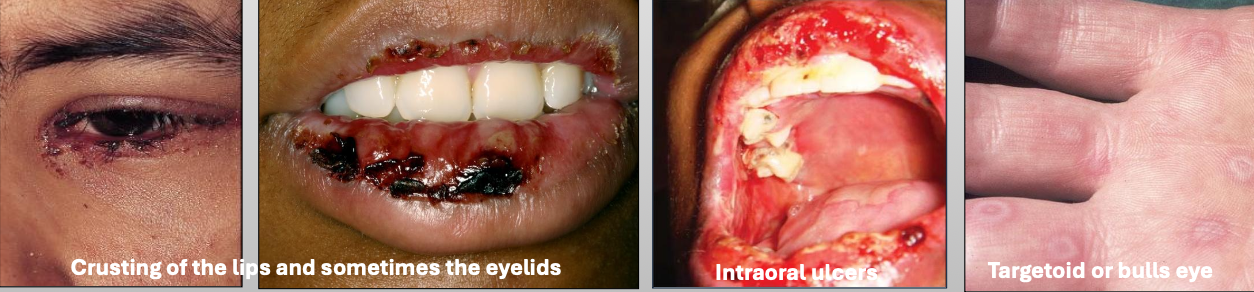

What is Erythema Multiforme (EM)

A blistering ulcerative mucocutaneous condition of uncertain pathogenesis. You see a spectrum of hypersensitivity reaction. The sisease lasts 2-6 weeks (self limiting); 20% have recurrent episodes

What is the cause of Erythema Multiforme (EM)?

Herpes virus (HSV)

Mycoplasma pneumoniae

Medications

What are the clinical features of Erythema Multiforme (EM)

You get prodromal signs a week before

Crusting of the lips and sometimes the eyelids

Intraoral ulcers

Targetoid or bulls eye

What demographic does Erythema Multiforme (EM) affect?

Young M>F

What is the treatment for Erythema Multiforme (EM)?

Steroids

IV rehydration

Topical anesthetic

Discontinue drug

What are characteristics of minor Erythema Multiforme (EM)?

Mild

Young, Male > female

Starts on skin of extremities, oral lesions appear

Crusting on lips

Usually due to herpes (HSV)

What are characteristics of major Erythema Multiforme (EM)?

Wide spread skin lesions + 2 or more mucosal sites

(Oral + ocular or genital)

Ocular scarring may occur in severe cases (Symblepharon)

Usually due to herpes (HSV)